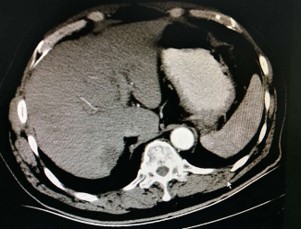

肝脏强化磁共振(2016.3.18)

肝脏强化磁共振示(2016.3.18):肝内散在可见结节状及团片状略长T1略长T2信号,信号不均匀,动态增强扫描病灶周边呈浅淡不均匀强化。提示:肝多发转移瘤。

治疗前:

治疗后:

疗效:PR,肝脏病灶缩小,肿瘤标志物下降。